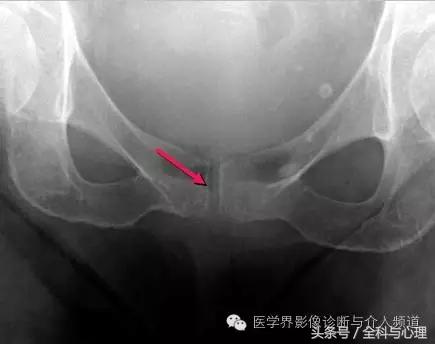

常见于膝盖、耻骨联合、臀部、尺骨三角纤维软骨复合体、肩关节。

耻骨联合软骨钙化